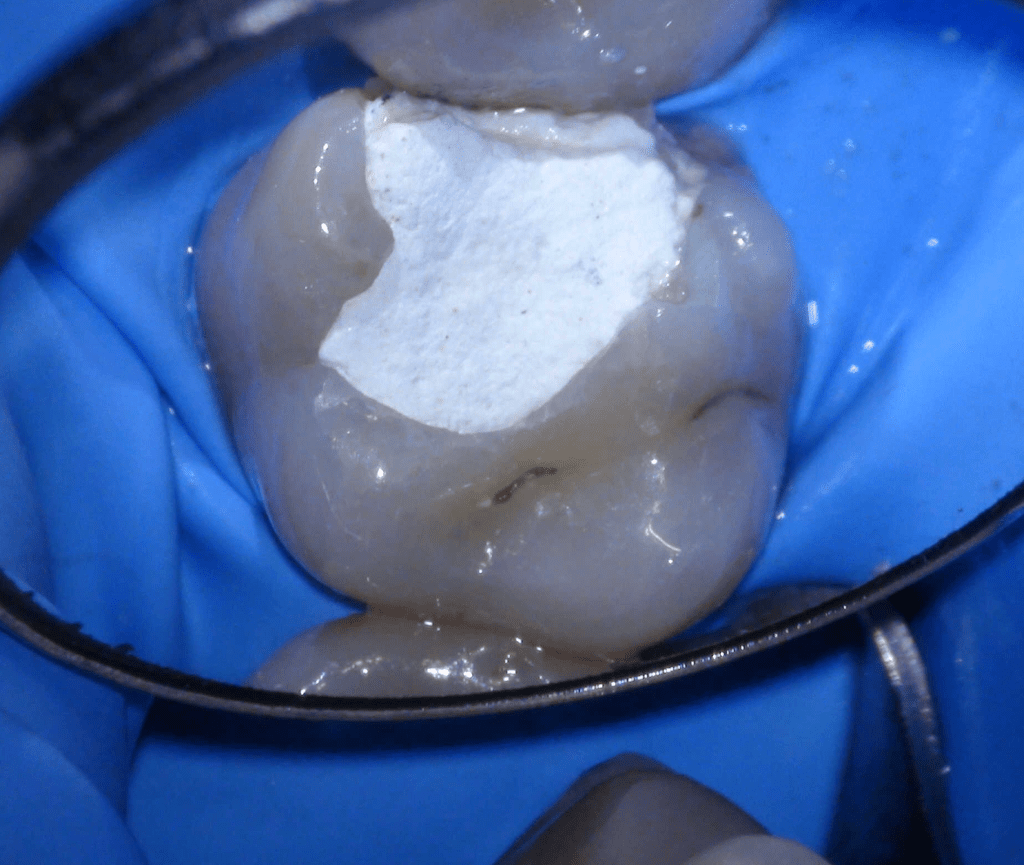

Fractura cuspídea tratable